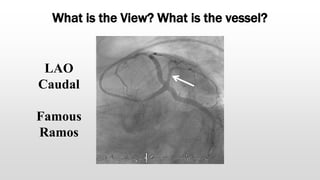

What is this View? What is this vessel?

What is the View? What is the vessel?

LAO

Caudal

Famous

Ramos